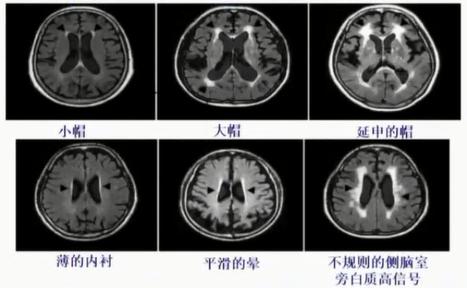

(1)Fazekas视觉评定量

Fazekas视觉评定量表可对脑白质损伤程度进行分级:

➤ 脑室周围:0=无;Ⅰ=帽状或者铅笔样薄层病变;Ⅱ=光滑晕圈;Ⅲ=不规则脑室周WMH,侵入深部脑白质。

➤ 深部(皮层下):0=无;Ⅰ=点状病变;Ⅱ=病变开始融合;Ⅲ=病变大面积融合。